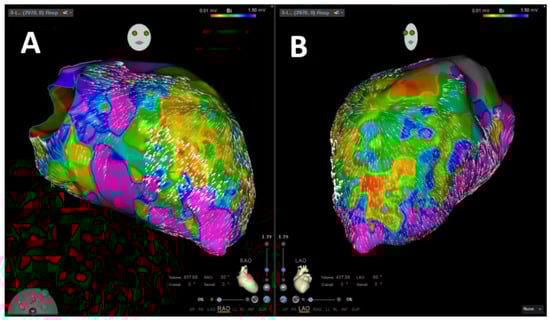

:1. Introduction

2.4. Coherent Mapping

4.1. Velocity Vector Mapping for Guidance of VA Ablation